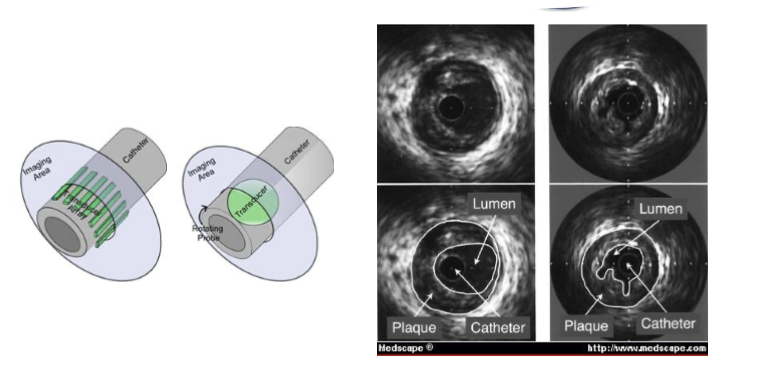

intravascular

multi or single element transducer

transducers can rotate or use an acoustic mirror